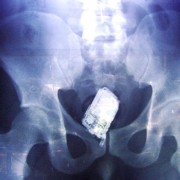

Можеби понекогаш се чувствувате виновно заради обилниот ручек што сте го изеле, но кога ќе видите што ставиле овие луѓе во својот стомак, ќе сфатите дека вие немате причина да се грижите. Барем не сте изеле батерии. Иако можеби имаат помалку калории, попрво би јаделе вкусни слатки со многу масти отколку киселински раствор. Луѓето имаат изедено некои многу чудни нешта…

Батерии